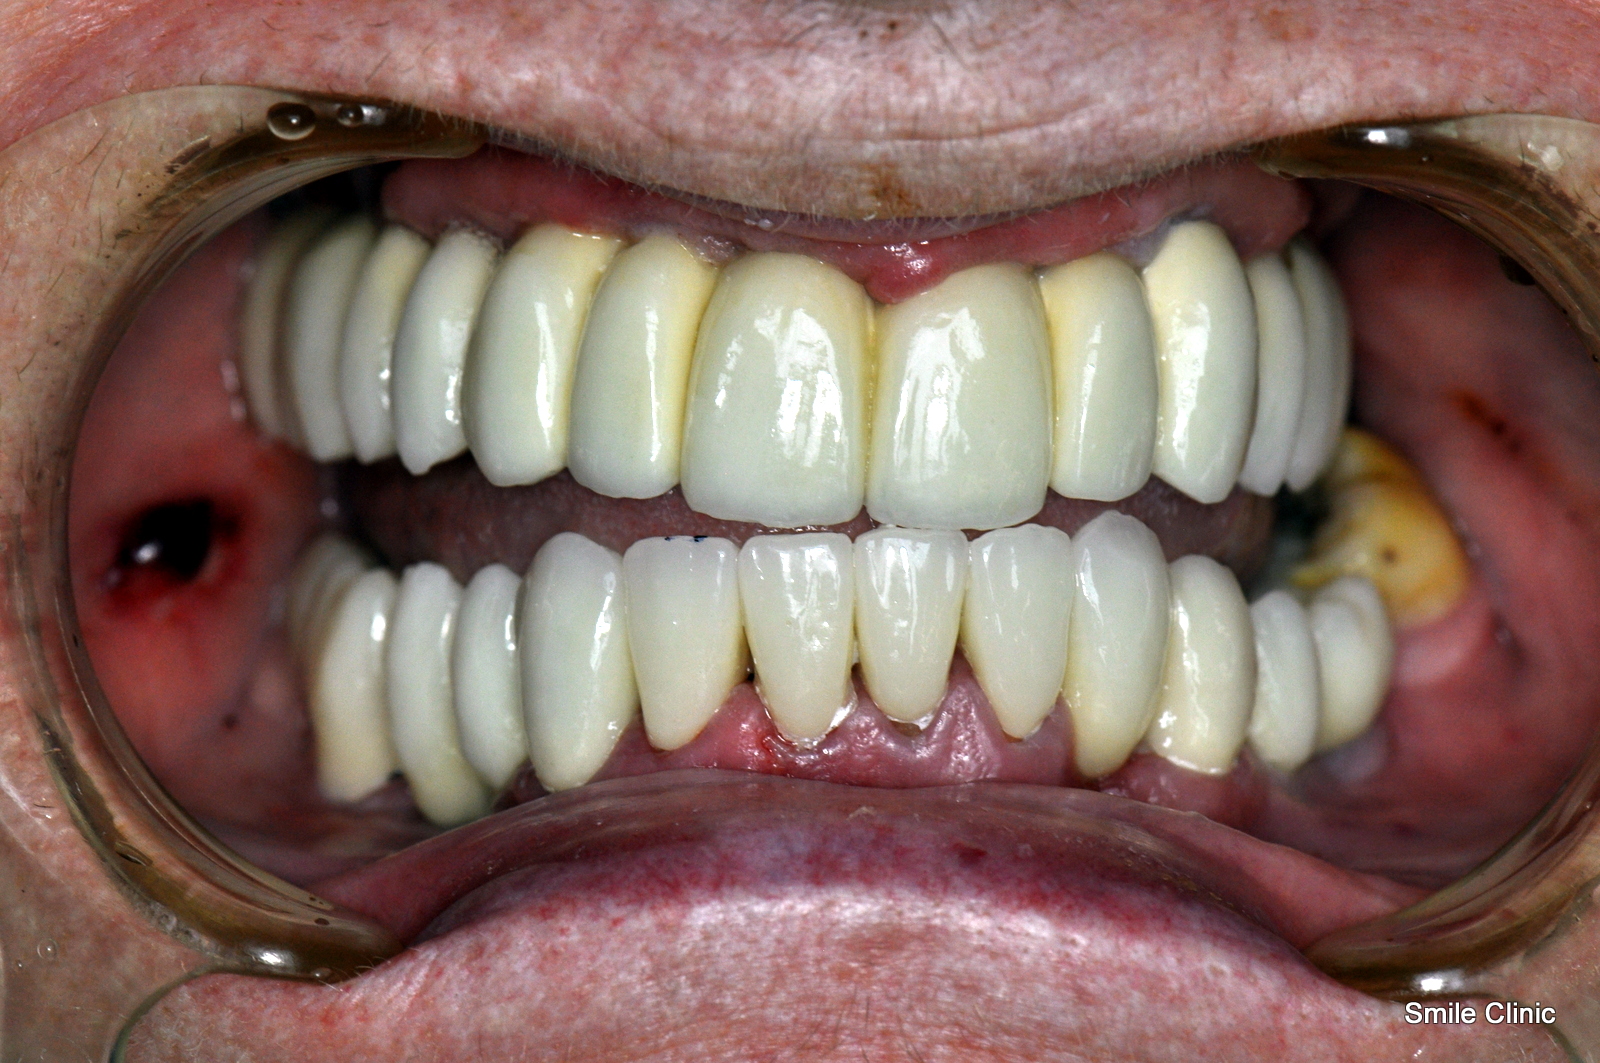

After over 100 email exchanges and a calming pill taken before treatment, in late November we finally got to begin our magic on Lynne’s smile. This involved placing 13 dental implants (7 to the upper jaw and 6 to the lower jaw) and then immediately replacing the denture and extracted teeth with a full semi-permanent bridge while the implants took 3-4 months to heal. (this specialty is only available in our clinic and included free with the overall treatment cost).

This amount of dental implants might sound like a lot, however especially in patients that have been using a denture (false teeth) for some time, the jawbone deteriorates and is not in the ideal condition to support a full jaw of teeth again. 2 visits later, 13 custom porcelain crowns in a bridge were created for both the upper and lower jaw – 26 in total as you can see from the x-ray here.